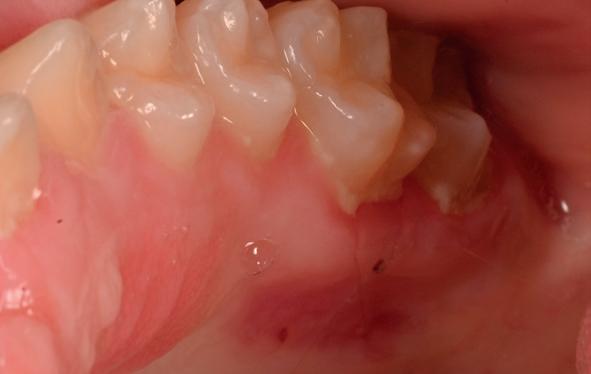

2. een tong met veel en diepe fissuren wordt vaak gezien bij patienten met een droge mond